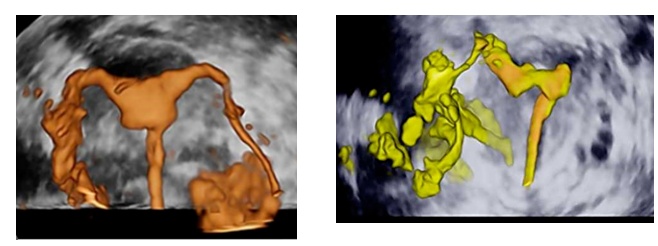

黑科技:3D/4D子宫输卵管造影

目前常用的检查就是3D/4D子宫输卵管造影,输卵管造影就是在医生的超声监视下,将代谢快、无毒性的新型微泡超声造影剂通过“宫腔置管”注入子宫腔,动态观察造影剂在子宫输卵管显影并流入盆腔,经过四维成像处理再现盆腔器官结构,输卵管腔得到实际的立体图像,输卵管阻塞具体位置也能一目了然了。

输卵管造影(左):双侧输卵管通畅/输卵管造影(右):左侧输卵管不通